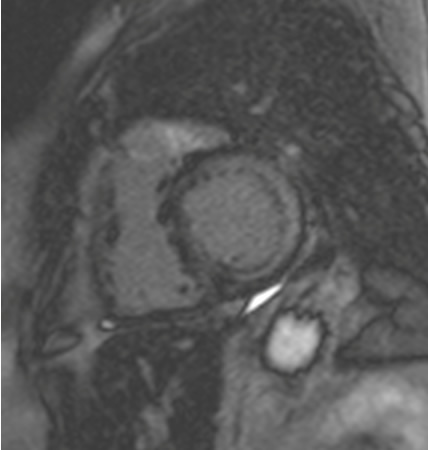

Ressonância nuclear magnética cardíaca (RNMC) de paciente com infiltração amiloide cardíaca. Após injeção de contraste de gadolínio, na fase tardia há um anel basal subendocárdico no ventrículo esquerdo (imagem de eixo curto basal)

Do acervo de Dr Jessica Webb; usado com permissão